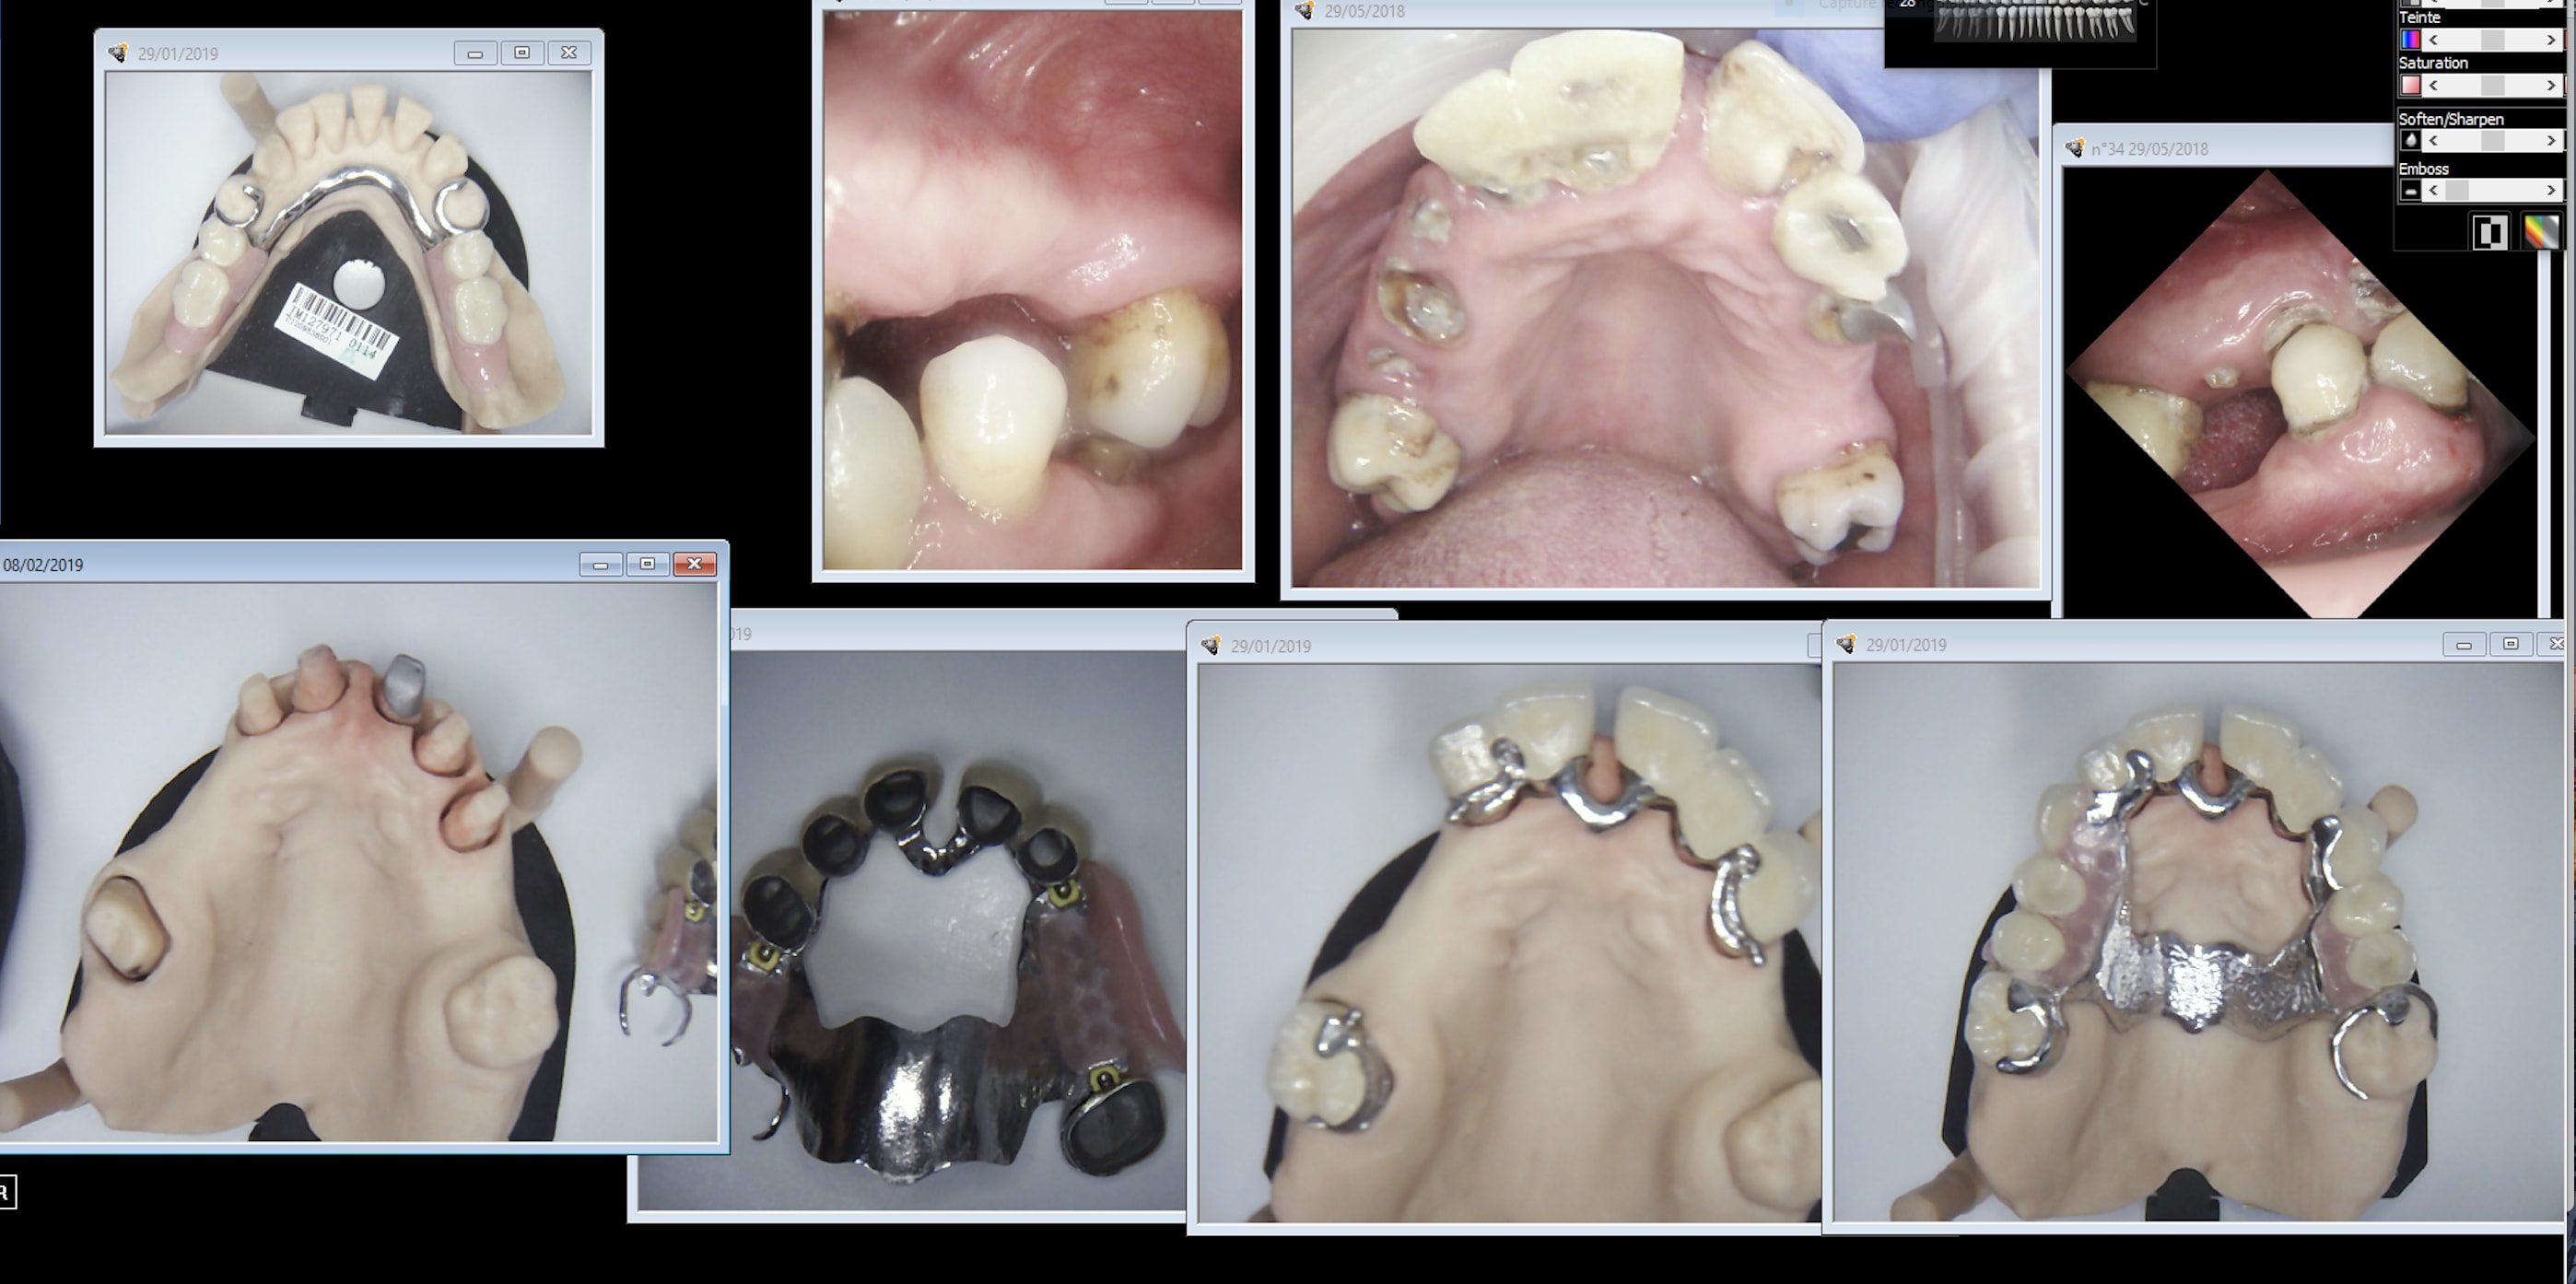

Bon, cas de réhabilitation globale: IC, couronnes fraisées, stellite.

One shot ou pas one shot?

https://www.meditlink.com/webViewer?shareKey=b3581946-3a41-4b89-a7a7-e7c69ce7827c

y'a de tout dans cette empreinte ! top !

Si ça rentre en One shot, c'est vraiment génial! Je vais quand même demander l'essayage des dents sur cire.

Tout dépend des couronnes . Si full anatomique oui , si céramique c’est possible mais , le stellite ne sera pas realisé sur l’empreinte numérique mais sur le modèle imprimé et scanné .

Je ne peux te donner que ce qui marche pour moi actuellement . Si couronnes monolithique , alors l’ensemble est réalisé en une passe . Sinon il faut re scanner et modélisé le stellite , ça fonctionne très bien , encore faut il une bonne maitrise de l’impression 3d.

One shot. Et on partait de très très loin. Il y a tout dans ce cas effondrement de la DV, over jet diastème ic coiffe direct attachements couronnes fraisées, over jet over bite stellitte haut, bas. Les provisoires sont restées 6 ans en bouche. Je commençais à m'inquiéter. -)))